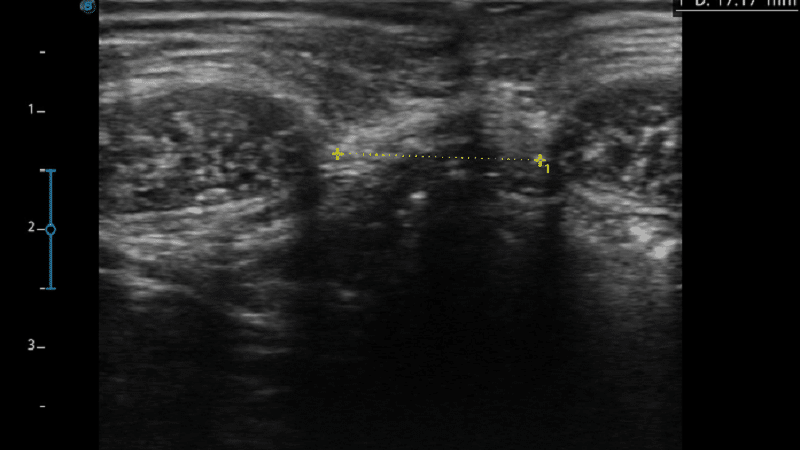

エコー写真は、M様の治療前後の効果を示しています。

治療後すぐから腹直筋離開が改善!

治療前 21.75㎜→治療後17.17㎜

(-4.58㎜ 離開 減少)

治療後も効果が残ることが分かった♪

治療を継続することで、腹直筋離開が改善することが判明した!!